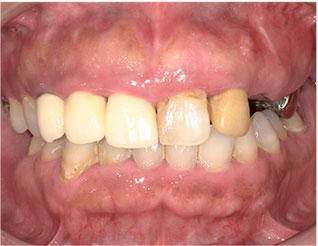

この方は歯並びもかなり悪く、虫歯も重度でした。

抜歯する歯もありましたがブリッジで治す事が出来ました。

1回目の治療時に仮歯を入れますのですぐに歯が入りますし、虫歯で欠けたりしている部分も無くなります。

当院のセラミック法でしたら歯並びも重度虫歯も一緒に治療が可能です。